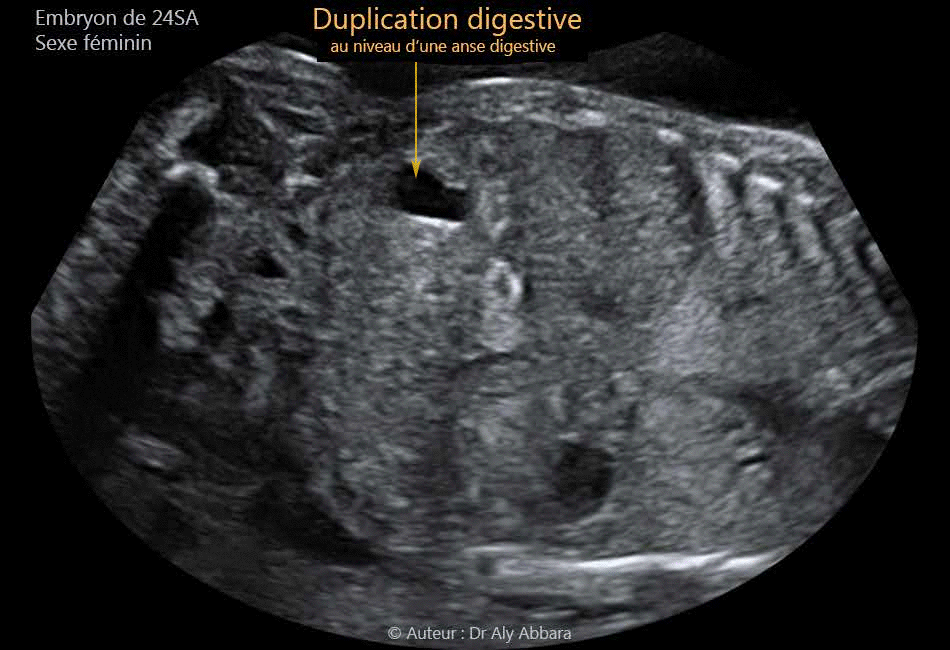

Images échographiques de duplication digestive intestinale chez un foetus agé de 24 SA

Images échographiques montrant une petite duplication digestive située au niveau d'une anse grêle (dans la flanc droit de la cavité abdominale) ; échographiquement cette duplication digestive se présente sous forme d'une formation anéchogène ou hypoéchogène (selon la coupe) tubulaire sur la coupe longitudinale et arrondie sur la coupe transverse ; elle mesure 13 x 7 x 7 mm de diamètre ; uniloculaire ; aux parois nettes hyperéchogènes ; sans lien anatomique avec le rein adjacent doit, ni avec le foie ou l'estomac.

Le contrôle échographique réalisé un mois plus ne montre pas d'évolution notable.

Foetus jumeau de sexe féminin de 24 SA d'âge

Les duplications des anses grêles se manifestent échographiquement comme une structure kystique ou tubulaire, hypo-échogène à paroi nette, de taille variable. Les sécrétions produites par la muqueuse digestive tapissant la paroi interne de ces kystes rendent leur contenu hypoéchogène avec parfois du méconium ou des calcifications.